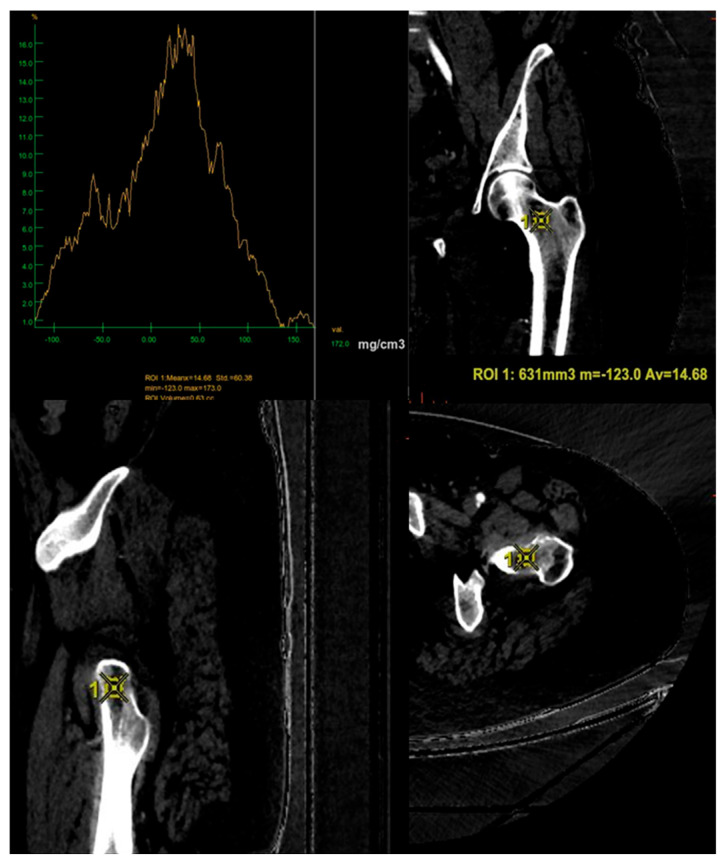

骨矿物质密度(BMD)的评估对骨质疏松症的诊断至关重要。双能x线吸收仪(DXA)是目前的金标准,但它在评估小梁骨方面有局限性,并且容易受到不同的伪影的影响。在这项研究中,我们评估了双能计算机断层扫描(DECT)是否可以作为一种替代方法来评估绝经后接受肿瘤随访的患者的骨密度。本研究对41例6个月内同时行DECT和DXA的患者进行回顾性分析。使用五种不同的基础材料对(BMPs)从DECT中提取骨密度值,并与股骨颈的DXA测量值进行比较。钙-脂肪配对与dxa衍生的骨密度相关性最强(Spearman ρ = 0.797),重复性好(ICC = 0.983)。DXA结果与各种BPM测量之间存在强烈而重要的关联。这些发现支持了当使用特定的BMPs时,DECT在精确和机会性评估BMD变化方面的可能性。这项研究表明,这项技术如何成为传统DXA的有用和有效的替代品,特别是当患者在使用DECT进行肿瘤随访时,最大限度地减少了额外的辐射暴露。

The assessment of bone mineral density (BMD) is essential for osteoporosis diagnosis. Dual-energy X-ray Absorptiometry (DXA) is the current gold standard, but it has limitations in evaluating trabecular bone and is susceptible to different artifacts. In this study we evaluate whether Dual-Energy Computed Tomography (DECT) can be defined as an alternative method for the assessment of BMD in a sample of postmenopausal patients undergoing oncological follow-up. In this study a retrospective analysis was conducted on 41 patients who had both DECT and DXA within six months. BMD values were extracted from DECT using five different base material pairs (BMPs) and compared with DXA measurements at the femoral neck. The calcium-fat pairing showed the strongest correlation with DXA-derived BMD (Spearman's ρ = 0.797) and excellent reproducibility (ICC = 0.983). There was a strong and significant association between the DXA results and the various BPM measurements. These findings support the possibility of DECT in the precise and opportunistic evaluation of BMD changes when employing particular BMPs. This study showed how this technique can be a useful and effective substitute for conventional DXA, particularly when patients are in oncological follow-up using DECT, minimizing additional radiation exposure.